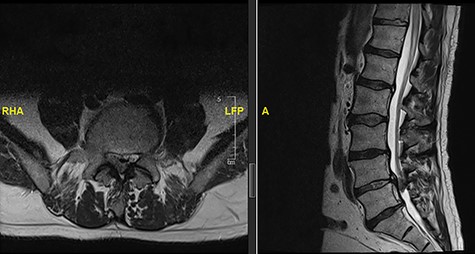

A 56-year-old male patient lumber decompression in a local neurosurgical centre for severe canal stenosis at L1/2 and L2/3 (Fig. 1) level after presenting with bilateral leg weakness and perianal numbness. Three months later he presented with recurrence of right leg pain radiating into the calf and worsening back pain as well as distal lower limbs weakness bilaterally with no sphincter problem. Following an magnetic resonance induction (MRI), which revealed a disc prolapse at L1/2 (Fig. 2), the patient was referred to our Centre. The images were reviewed by a consultant radiologist and as a possibly of intradural herniated disc disease was described. Intraoperatively no extradural disc prolapse was found, so midline durotomy was performed. Intradural disc herniation (IDH) was identified, which was communicating with the disc space through a midline defect in anterior dura (Fig. 3). This was removed extracted under the microscope. Post-operatively, he had a CSF leak needing re-suturing of dura. The patient did make a good post-operative recovery with no major sensory or motor deficits or sphincter disturbance.

Initial MRI images prior to index procedure revealing stenosis at L1/2 and L2/3.

MRI image revealing a recurrence of a disc prolapse, suspected to be an intradural disc at L1/2, confirmed intraoperatively.